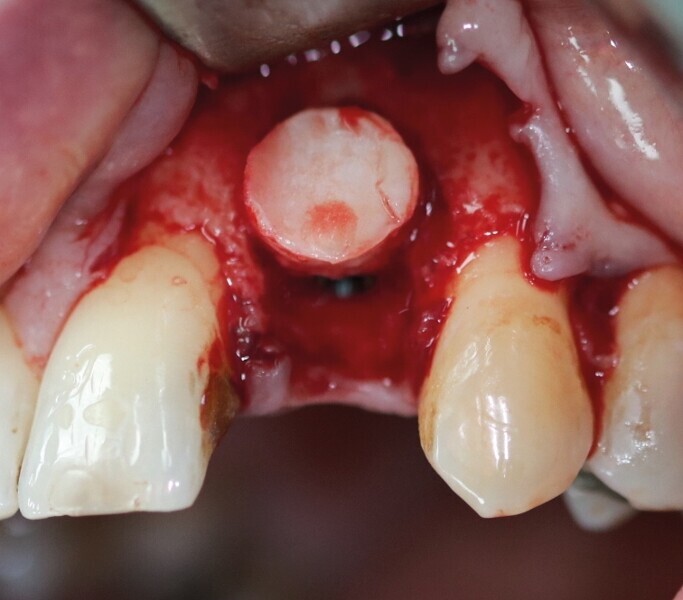

Pour connaître la profondeur de trépanation, il suffit d’enfoncer la sonde parodontale et de mesurer l’épaisseur de gencive sur l’os. En y ajoutant 4 mm, la profondeur finale est obtenue pour avoir suffisamment d’os. Une fois la carotte ostéogingivale prélevée (Figs. 23 et 24), il ne faut pas séparer l’os de la gencive, mais réduire l’épaisseur gingivale en supprimant la partie kératinisée (Fig. 25). Un implant cylindroconique (Straumann BLT 3,3 SLActive Roxolid) est parfaitement ancré (Fig. 26). La carotte d’os et sa gencive toujours adhérente, sont alors impactées transversalement à l’implant (Fig. 27). La partie osseuse spongieuse est au contact de l’implant, pendant que le conjonctif qui y est attaché, est utilisé comme un greffon conjonctif enfoui sous le lambeau vestibulaire.

Cette technique devient alors une combinaison entre la greffe osseuse simultanée à l’implant, décrite dans le premier cas clinique, et une greffe gingivale (Figs. 28 et 29). Lorsque la stabilité primaire est importante, la mise en esthétique peut être envisagée. Ce sont les implants cylindroconiques qui donneront le meilleur ancrage. Des points de suture matelassiers verticaux plaquent et repositionnent verticalement les papilles interdentaires (Monofilament Seralon 5.0).